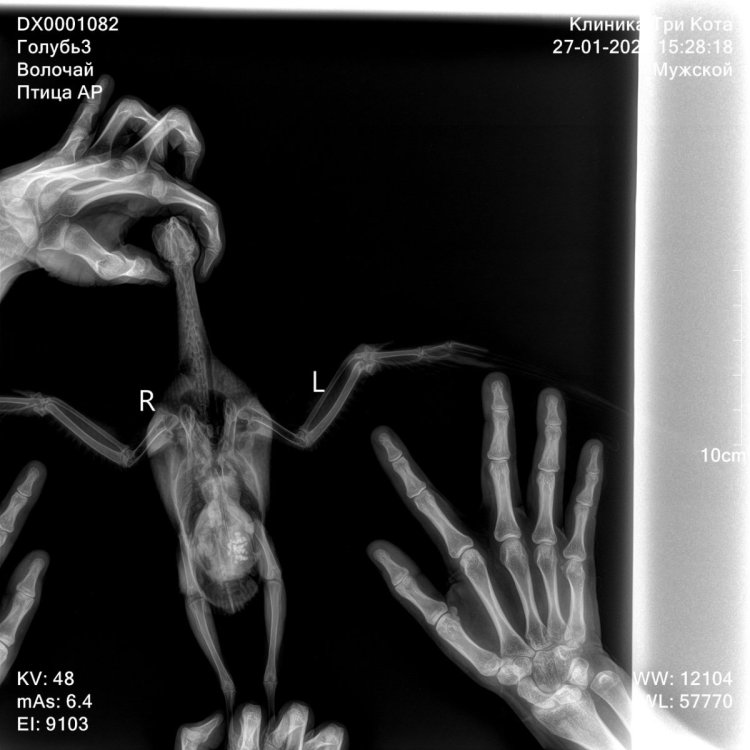

@свс у нас брали помет на анализ, но не включили его в стоимость, так как «там ничего такого, бактерии как и у всех уличных». Спасибо на этом 😂 и дополнительно взяли анализы на сальмонеллез и микобактериоз (анализов еще нет) честно немого в шоке с неправильных доз, потому что мы именно к ней всегда ездим и по ее дозам лечимся Это вот что мы делали микроскопия кала не включена но сделана пошла фоткать все что вы написали

рентген покажите @Zosia